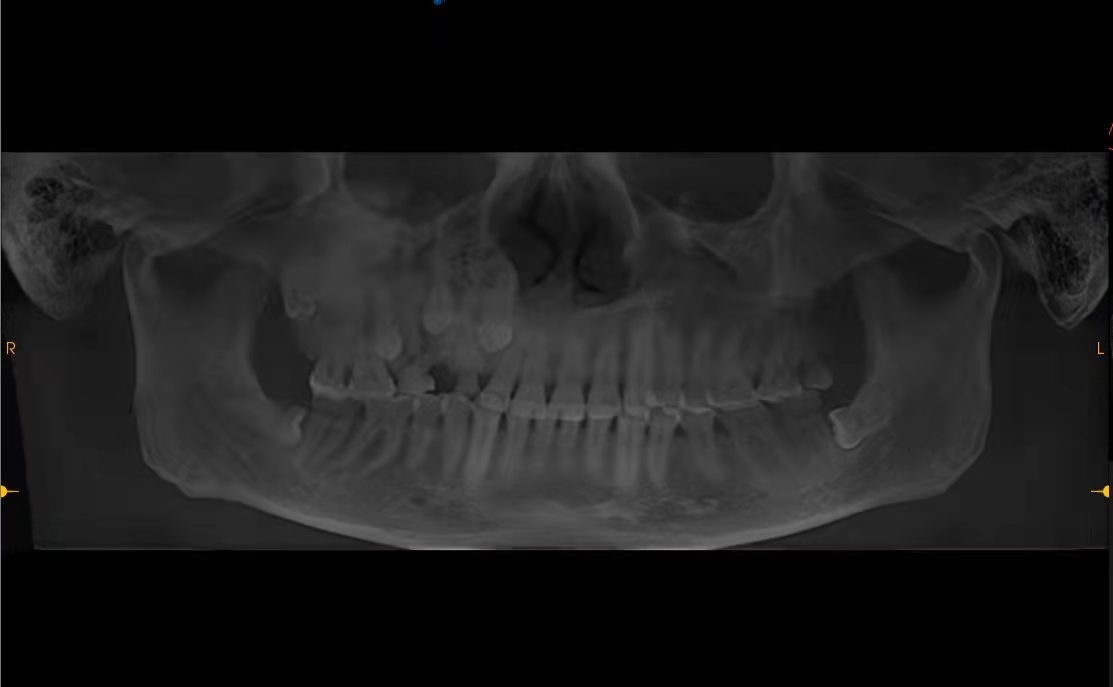

检查片上清晰可见,有3颗牙“埋伏”在鼻子部位。

1月初,王先生到武汉大学中南医院求诊,耳鼻喉头颈外科和口腔科联合会诊发现,王先生右侧上颌骨骨质非常坚硬,原本在30多年前就应该自然脱落的3颗上槽牙无法正常脱落,而对应的3颗恒牙由于被乳牙“鸠占鹊巢”,竟然反向生长进入上颌窦成为“埋伏牙”,随着时间流逝,这3颗“埋伏牙”持续刺激上颌窦,并导致慢性鼻窦炎久治不愈。